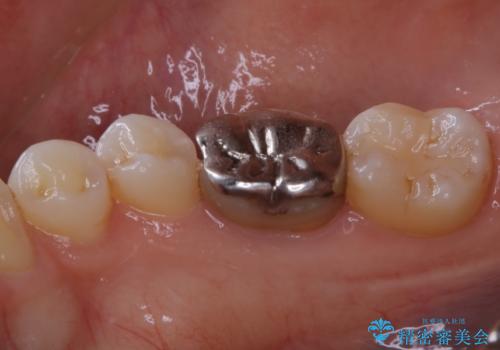

適合不良の補綴物は二次的な虫歯発生のリスクが高まります。

自費診療で用いられる材料は保険適応の材料に比べて、より精密で適合の良い被せ物作ることができるため、長期的な虫歯のリスクを大幅に減らすことが可能です。

右上の被せ物についても今後治療介入していく予定です。